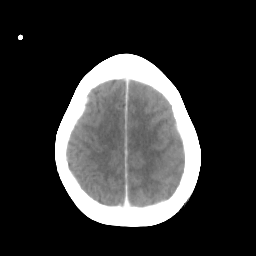

Metastatic bronchogenic carcinoma: Roentgen-ray CT -- Slice #18

[Home][Help][Clinical] Slice 18